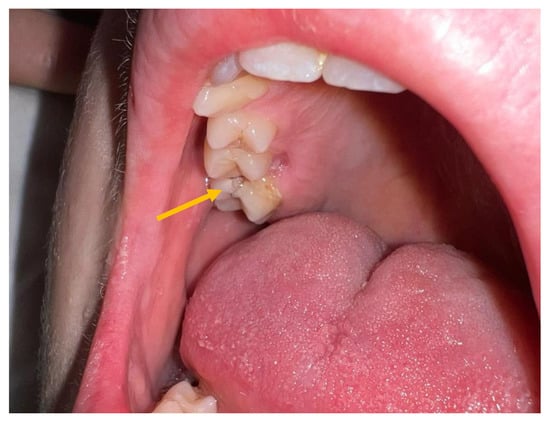

2. Case Report